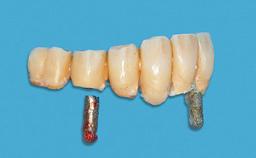

Improving an Existing Implant-supported Denture in an Alzheimer Patient with Bipolar Affective Disorder with Moderate Depression and Dementia

An 83-year-old man presented together with his caregiver at the dental department of the Medical University of Innsbruck, Austria with complaints of swelling in the right maxillary canine area and loss of retention of his 5-years-old mandibular denture. The patient had a significant medical history (20 years) of bipolar affective disorder with moderate depression (F 31.3) and dementia in Alzheimer’s disease (F 00.2). The patient had been in ambulant psychiatric therapy for his depressive illness for the past 20 years. He lived alone and had no children; his sister assisted with daily living. She reported that the patient exhibited compulsive hoarding behavior. In the previous two months, she had noted increasing disorientation and vertigo in the patient. She therefore accompanied him for a medical consultation at the Department of Psychiatry and Psychotherapy of the Medical University of Innsbruck. He was released home after a 6-week inpatient stay.

# of Implants 2

Type of Implants One-Piece

Attachment One-Piece

Prosthesis Type RDP

Defining Characteristics Fully edentulous lower jaw to be rehabilitated with an implant-borne removable overdenture